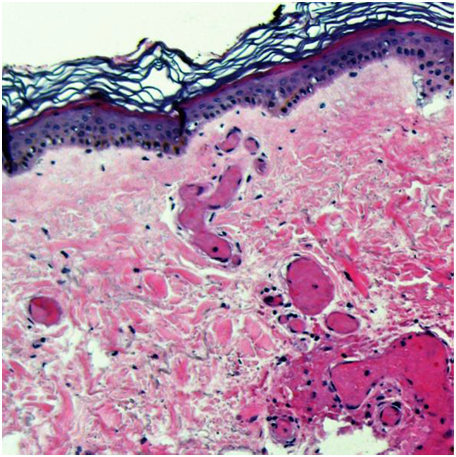

His warfarin was held and the patient was admitted for further work up. Our initial differential diagnosis included hematoma, pyoderma gangrenosum, venous gangrene, purple toe syndrome, cryofibrinogenemia, steven Johnson Syndrome, Vibrio Vulnificus Infection, hemangioma, pyoderma gangrenosum, heparin induced skin necrosis and Warfarin Induced Skin Necrosis. His protein C level was low on further work up. Bedside skin biopsy was performed which showed diffuse dermal microthrombi with endothelial cell damage and red cell extravasation with full-thickness coagulative necrosis (Figure 2), confirming diagnosis of warfarin induced skin necrosis. Patient was discharged home without warfarin and his skin lesion completely resolved with local wound care.

Figure 2 Skin biopsy showing diffuse dermal micro thrombi with endothelial cell damage and red cell extravasation with full-thickness coagulative necrosis.

The diagnosis of warfarin induced skin necrosis is made clinically. Skin biopsy can aid in diagnosis. It usually reveals clotting within blood vessels in the skin without any inflammation. Blood test for levels of protein C and protein S is important to determine any predisposing factors.3